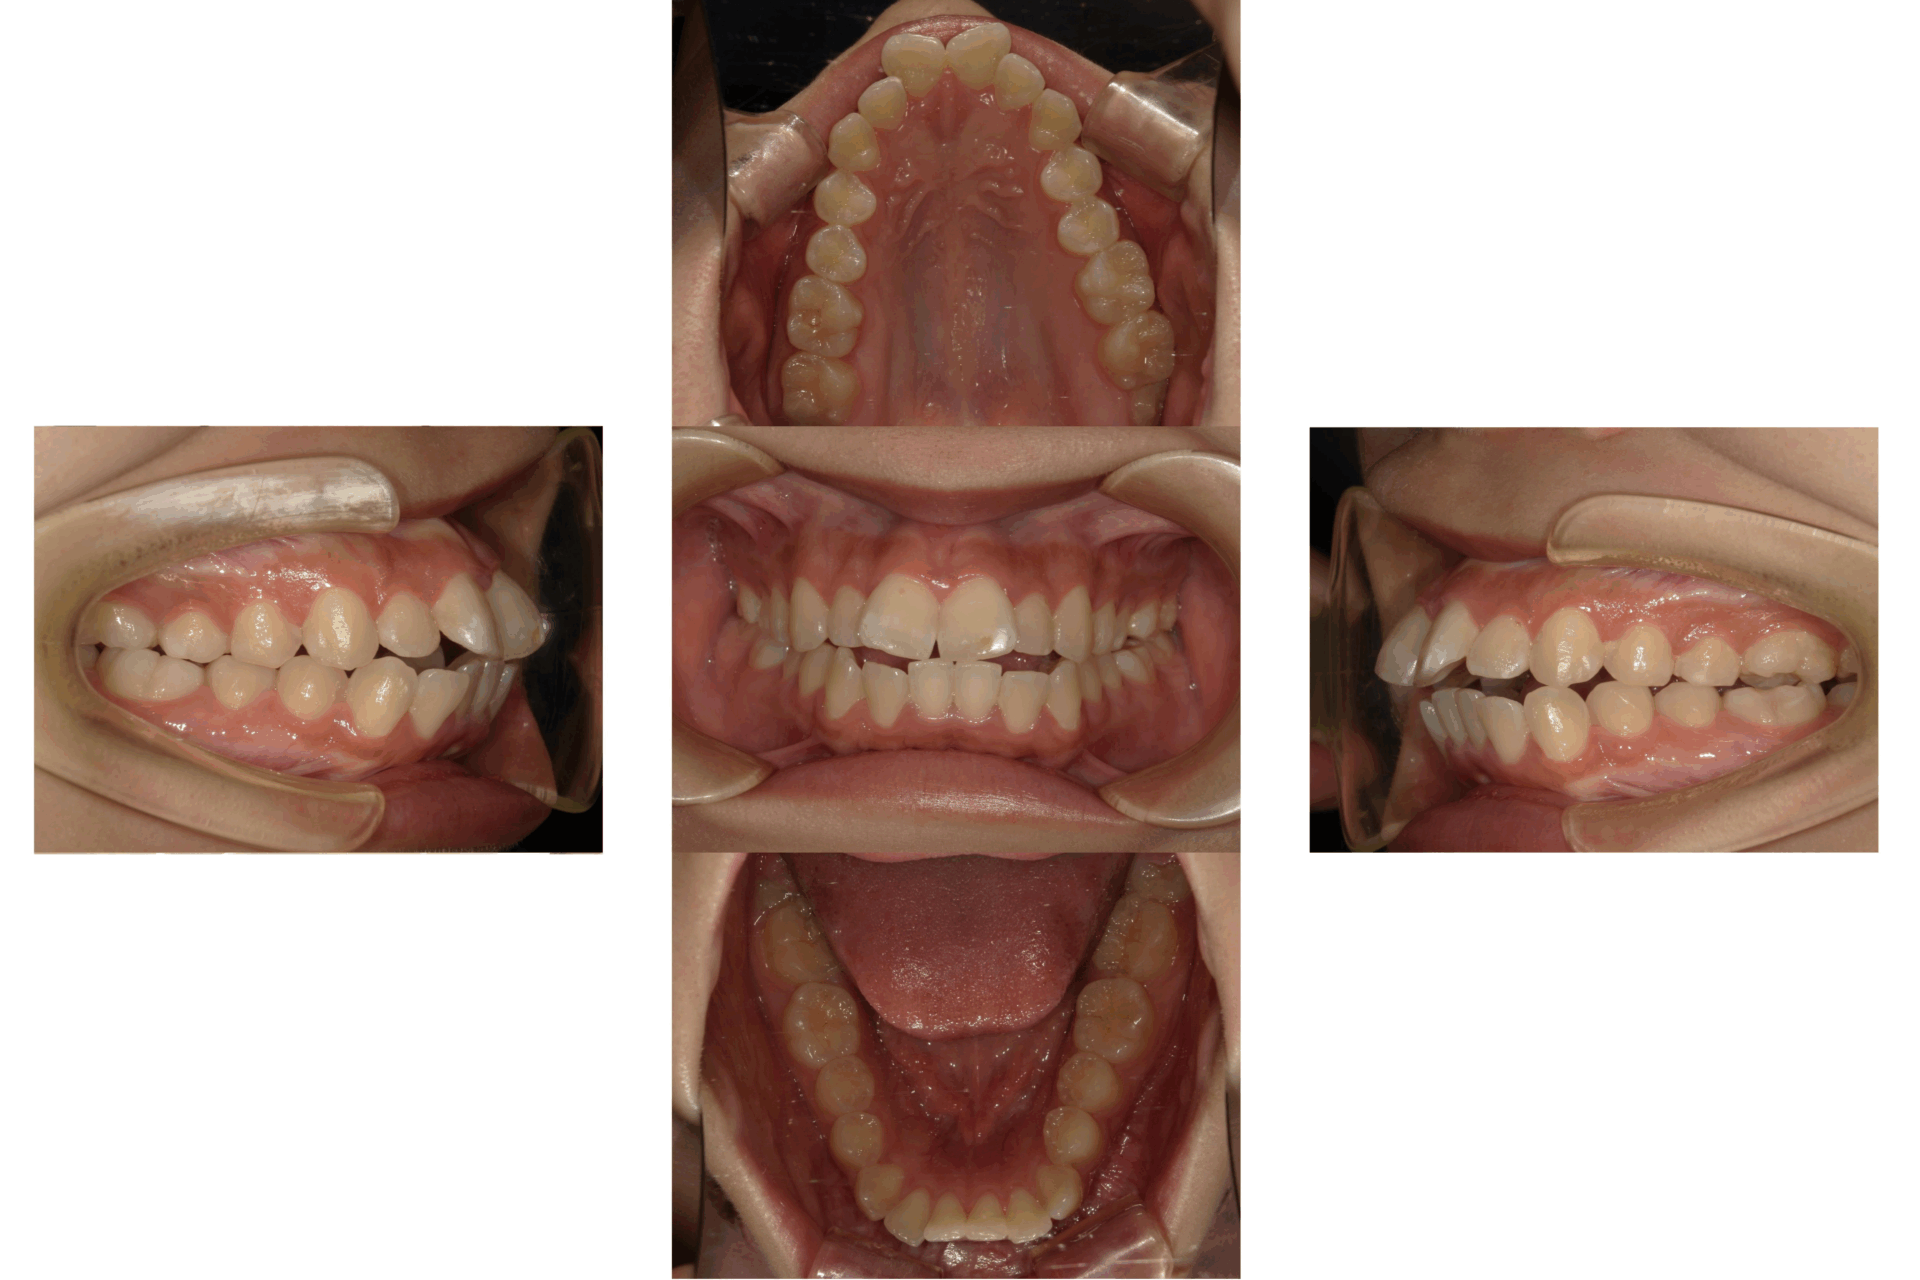

10代、女性、ワイヤー

| 施術内容 | 主訴:上下前歯でこぼこ。なるべく抜きたくない。 詳細:ワイヤー矯正での歯並び改善 詳細:ワイヤー矯正での歯並び改善 歯肉炎リスクあるため、今後は後戻りのチェックとともに歯肉炎管理もしていきます。 |

| 治療期間 | 12ヶ月(2/6現在 治療終了) |

| リスク・副作用 | ■リスク・副作用 ・治療の初期段階では、痛みや不快感が生じやすくなりますが、一週間前後で慣れます。 ・歯の動き方には個人差があるため、予想された治療期間より延長する場合があります。 |

| 費用 | ワイヤー矯正 60万円(税込660,000円) |